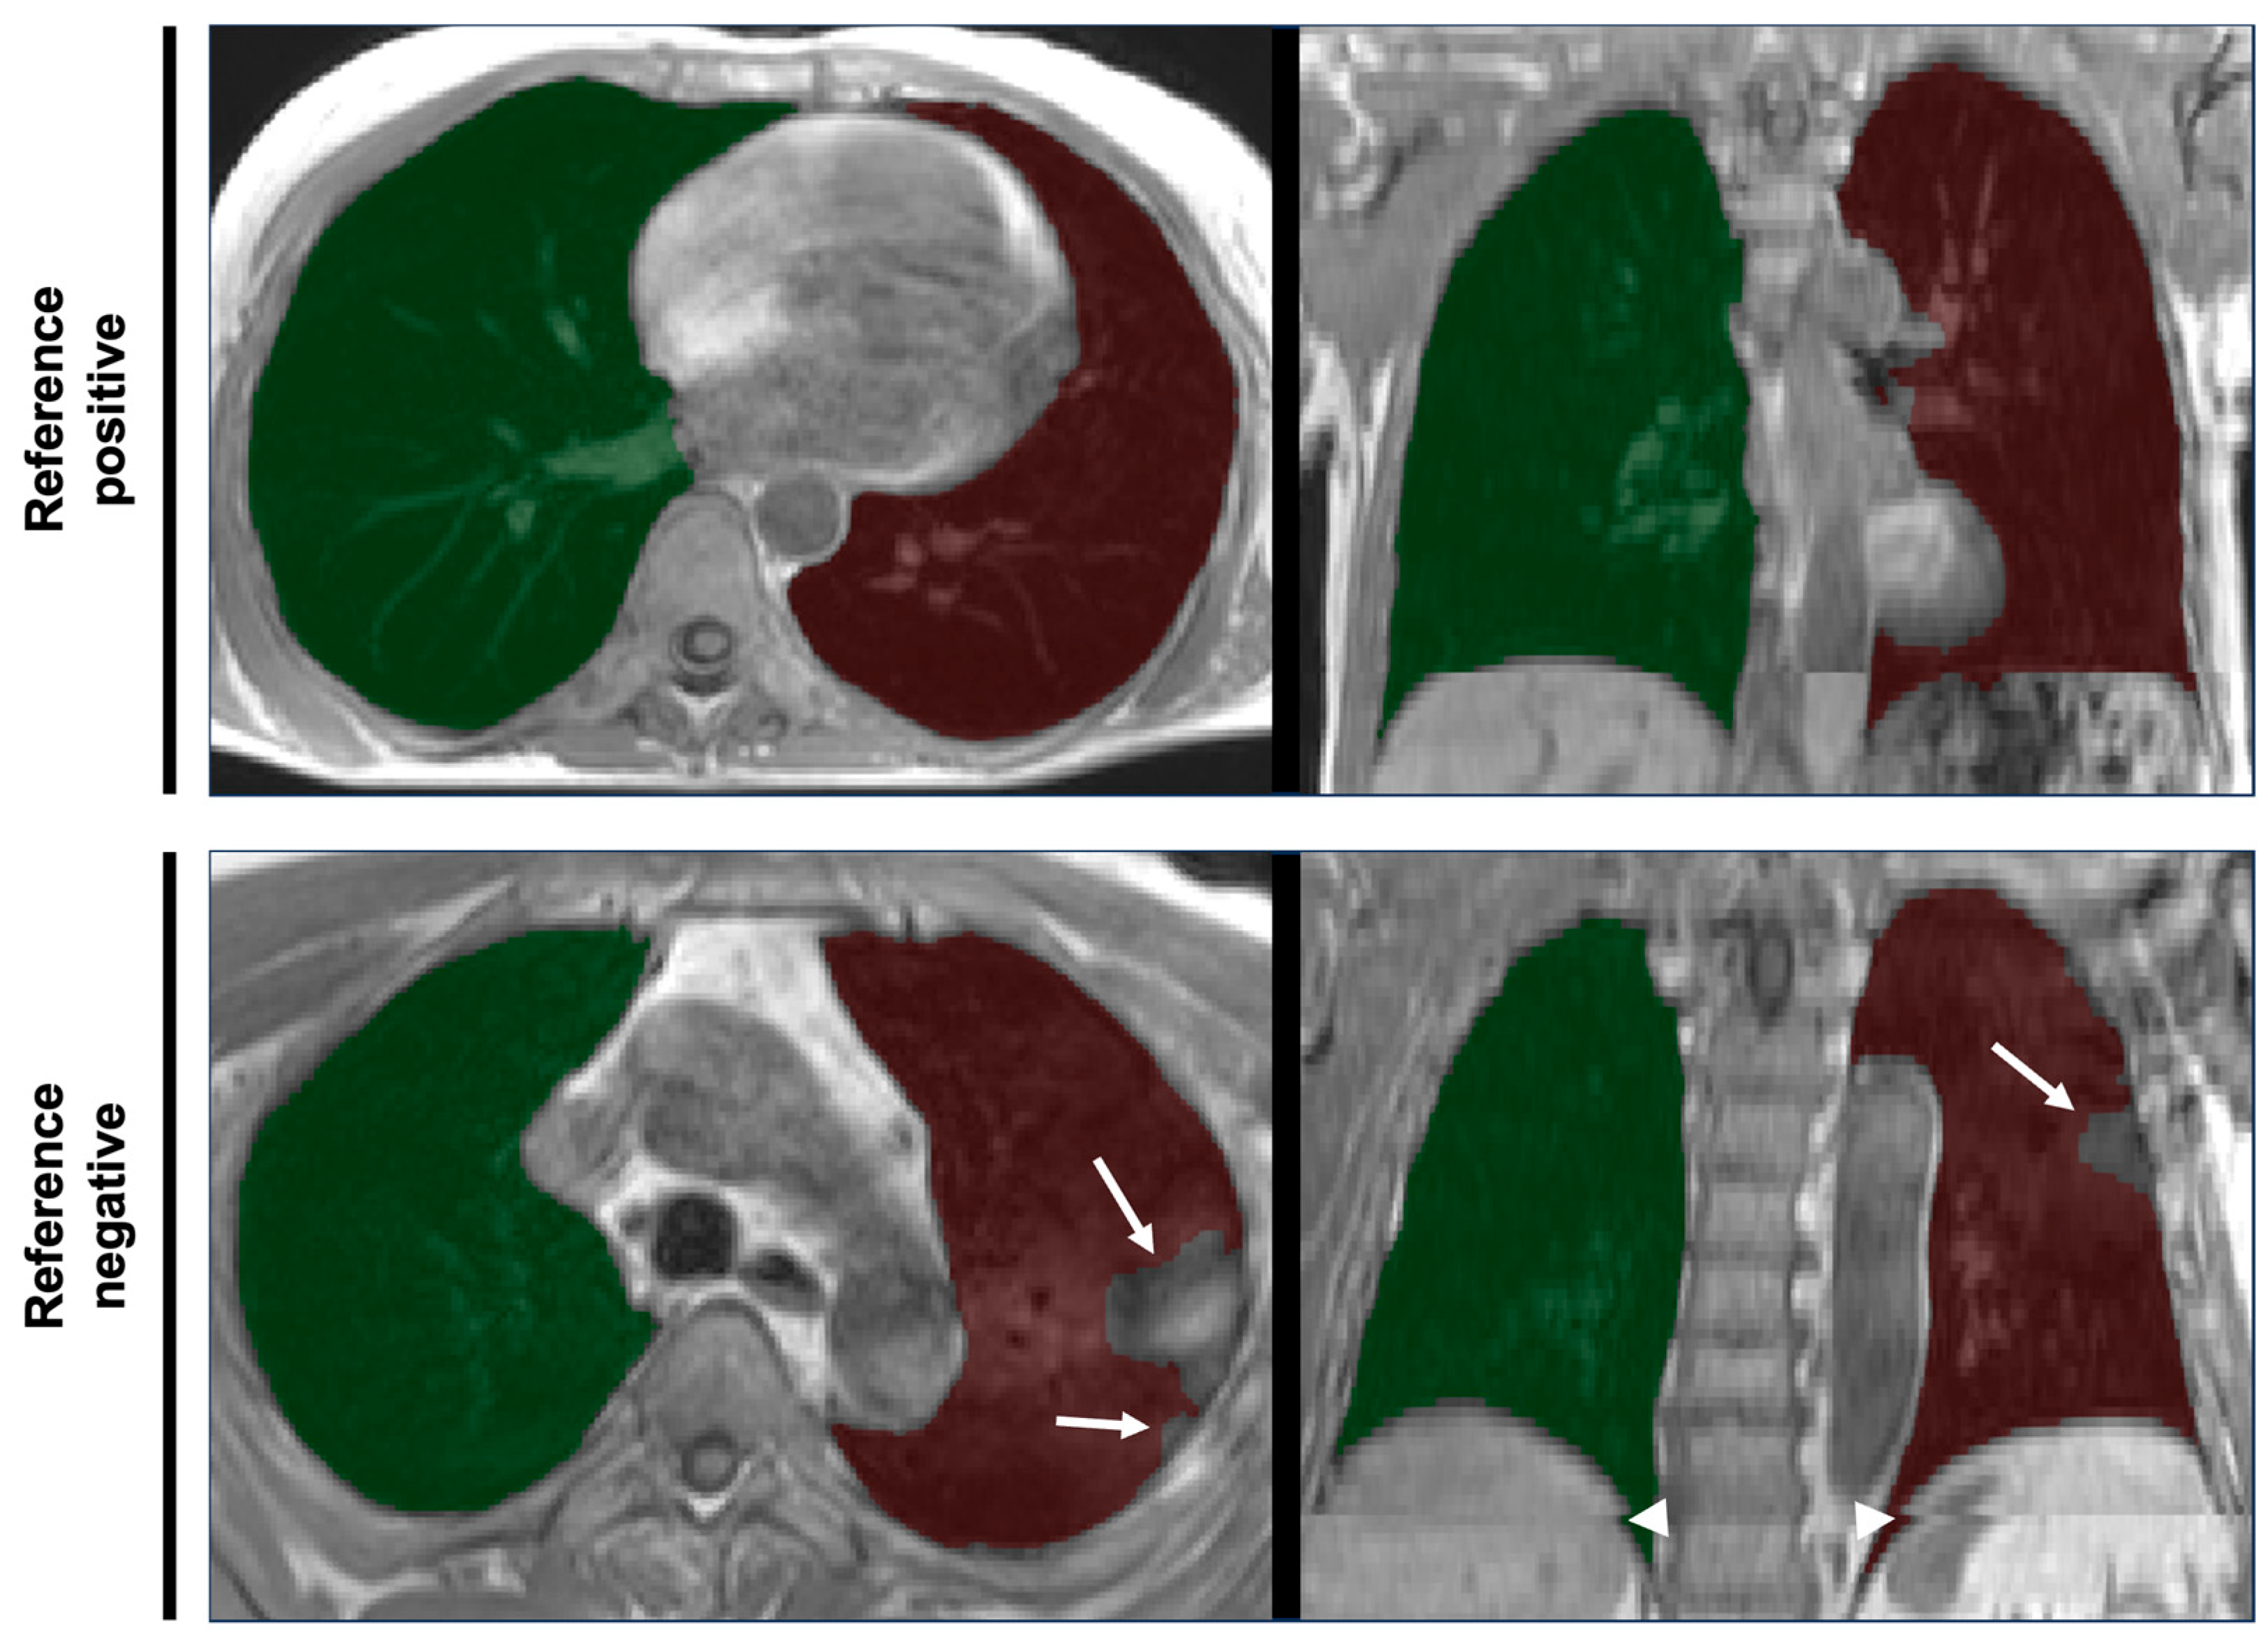

2.2. MR Imaging

Whole-body MRI scans as part of NAKO were conducted at five study centers and are described in detail elsewhere [6]. In brief, lungs were covered in an axially acquired T1-weighted 3D VIBE two-point DIXON sequence of thorax and abdomen in inspiratory breath-hold (slice thickness 3.0 mm, voxel size in-plane 1.4 × 1.4 mm) using 3T MRI scanners (MAGNETOM Skyra, Siemens Healthineers AG, Forchheim, Germany). Examples are provided in Figure 1.

Figure 1. Examples of thoracic MRI data and overlying lung segmentation masks. Axial slices (left column) and coronal views (right column) of the thoracic part of axially acquired T1-weighted 3D VIBE two-point DIXON images of thorax and abdomen of two different participants of the NAKO study. Translucent overlays of right (green) and left (red) lung segmentation masks as results of deep learning-based automated segmentation are shown. The quality of the lung segmentation of the participant in the top row was deemed sufficient for further analysis (reference positive). The bottom row shows an example of erroneous segmentation according to the reference standard (reference negative). Note the exclusion of consolidated parts of the lungs (arrows) and the spatial inconsistencies (composing artifacts, arrowheads) resulting from the stitching of separate acqusitions for the lower and upper part of the scan volume.